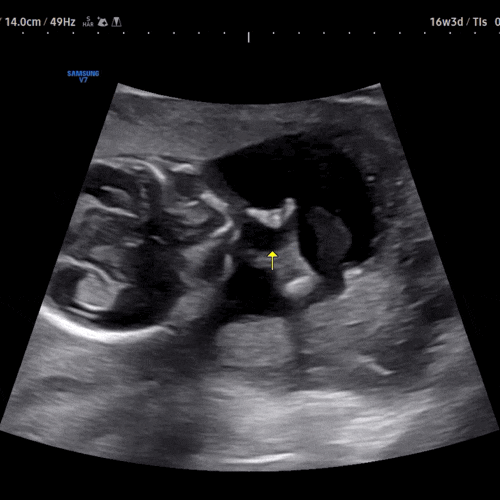

임신 12~16주 기록

드디어 임신16주!! 임신초기 금방지나가네요 배도 제법 나오고 밥먹으면 만삭되는 ㅋㅋㅋ 태동은 아직입니...